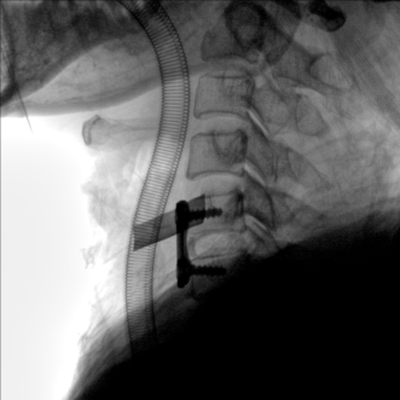

臨床適用科室:骨科、普通外科、矯形外科、創(chuàng)傷外科、泌尿外科、脊柱外科、疼痛外科、消化科、婦科等科室。

大尺寸動態(tài)平板探測器,高DQE、低噪聲、圖像清晰。采用多分辨率圖像增強(qiáng)處理技術(shù),不同部位不同圖像處理算法,滿足客戶多樣化的需求。

圖形化操控界面設(shè)計:設(shè)有多種人體特征攝影參數(shù),操作簡便。雙向紅光十字定位系統(tǒng):實現(xiàn)無射線下的高效定位。信息共享:遵循DICOM3.0格式接口,可無縫對接云PACS系統(tǒng)。